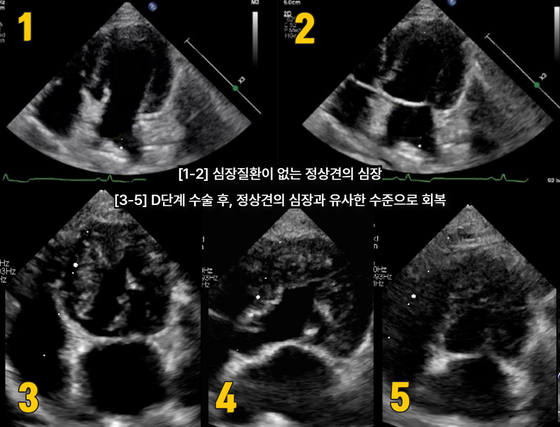

D단계 수술 후, 정산견의 심장과 유사한 수준으로 회복된 반려견의 심장초음파(넬동물의료센터 제공) © 뉴스1

담당 수의사는 판막을 지지하는 조직의 길이를 조정하고 판막과 주변 구조를 교정하는 수술을 시행했다. 수술 후 심장초음파 검사에서 환견의 판막 기능이 정상견과 유사한 수준으로 회복된 것으로 나타났다.